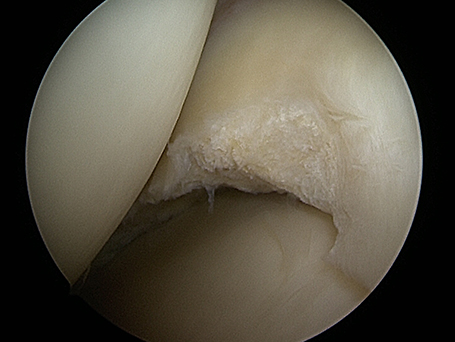

Bild inneres Kompartiment

Arthroskopie: Inneres Kompartiment

Innenmeniskuseinrisse durch Verschleißleiden mit belastungsabhängiger innenseitiger Symptomatik. Intraoperativ deutliche Zerfaserung des gesamten Randes des Innenmeniskus insbesondere im Hinterhornbereich. Nach arthroskopischer Säuberung glatter stabiler Restmeniskus bei nur geringem Knorpelschaden. Außenseitiges Gelenk ohne Zeichen des vorzeitigen Verschleißes. Nach dem ambulanten Eingriff ist eine schmerzadaptierte Belastung an Gehstützen erlaubt. Regelmäßiges Kühlen. Die meisten Patient*innen können nach 10 - 14 Tagen schon eine alltagstaugliche Belastung des Kniegelenkes durchführen.

Bild deutliche Mehrfacheinrisse des Innenmeniskus im Knie

Deutliche Mehrfacheinrisse des Innenmeniskus im Knie